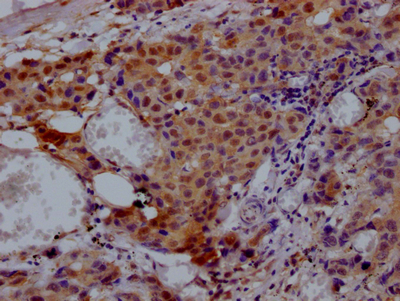

IHC image of CSB-RA215300A0HU diluted at 1:100 and staining in paraffin-embedded human breast cancer performed on a Leica BondTM system. After dewaxing and hydration, antigen retrieval was mediated by high pressure in a citrate buffer (pH 6.0). Section was blocked with 10% normal goat serum 30min at RT. Then primary antibody (1% BSA) was incubated at 4°C overnight. The primary is detected by a Goat anti-rabbit polymer IgG labeled by HRP and visualized using 0.05% DAB.